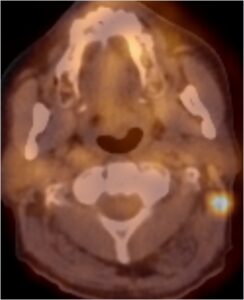

Εικονα τραχηλικης λεμφαδενιτκης μεταστασης στο PET/CT: η μετασταση παρουσιαζεται ως υπερμεταβολικη εστια στον ΑΡ τραχηλο